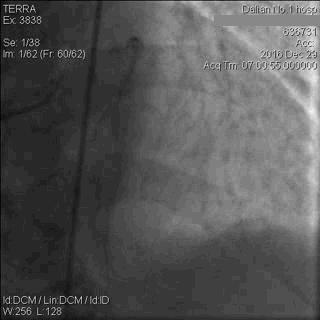

CAG显示,患者LAD中段以下闭塞;LCx近段轻中度狭窄,远段重度狭窄,钝缘支(OM)开口闭塞;RCA细小,且伴弥漫性轻中度狭窄,如图5。

图5 急诊CAG图像